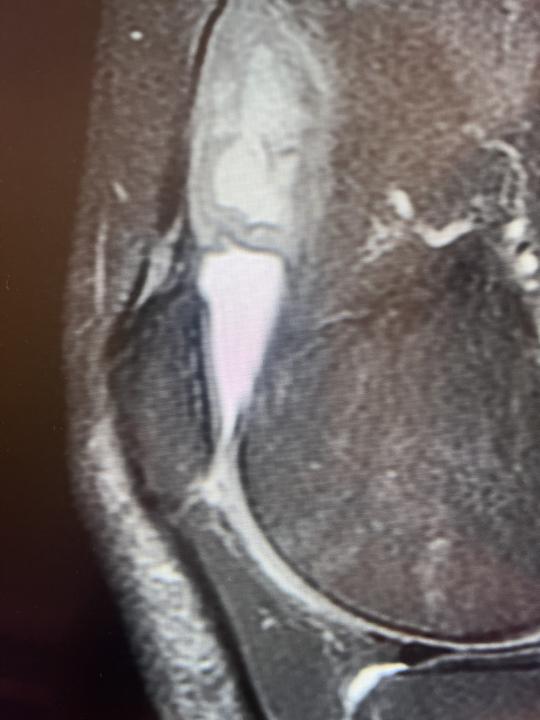

Knee pain

57 yo female with knee pain. Baker cyst was suspected by referring physician. I can see small amount of fluid in SB and partial cartilage loss on MFC. On the lateral side of femoral bone I suspect thrombosis of varicose vein. Can you agree or do you have another suggestions?

0 likes • Aug 3